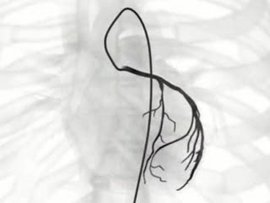

字脑科医院李振并主任超选择性全脑血管造影术